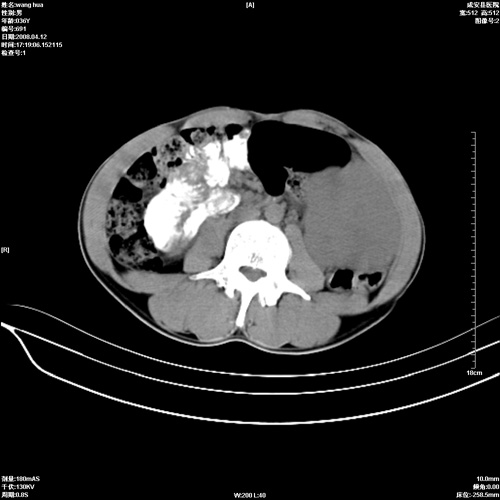

标题: CT12809:男36岁,自感上腹胀5天,B超诊断为脾肾之间占位,血 [打印本页]

标题: CT12809:男36岁,自感上腹胀5天,B超诊断为脾肾之间占位,血

有没有外伤史呀!没有也要考虑自发性脾破裂可能。不除外脾恶性占位可能。

脾脏血管肉瘤的可能。增强意义不大。

脾脏明显增大,其内见巨大低密度灶,境界不清,病史较短,考虑恶性病变脾血管内皮细胞肉瘤可能。建议增强扫描与脾脏淋巴瘤及血管瘤鉴别。